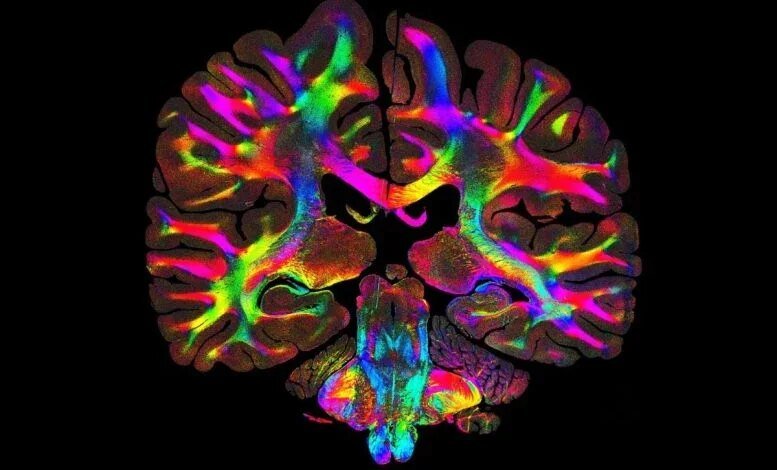

الإعداد التجريبي بسيط، ولا يتطلب سوى مصدر ضوء LED دوار وكاميرا مجهرية. تقوم خوارزميات الكمبيوتر بعد ذلك بمعالجة الاختلافات الدقيقة في الضوء المتناثر لإنشاء خرائط مرمزة بالألوان تُعرف باسم توزيعات توجيه الألياف المبنية على البنية المجهرية، والتي تُظهر اتجاه الألياف وكثافتها.

لقد كان رسم خرائط التوصيلات المجهرية للدماغ منذ فترة طويلة هدفًا رئيسيًا في علم الأعصاب. باستخدام ComSLI، تمكن جورجياديس وزملاؤه من تصور كامل أجزاء الدماغ البشري المثبتة بالفورمالين والمضمنة بالبارافين، بالإضافة إلى شرائح ذات حجم قياسي، مما يكشف عن تفاصيل هيكلية دقيقة عبر مناطق الدماغ المختلفة.